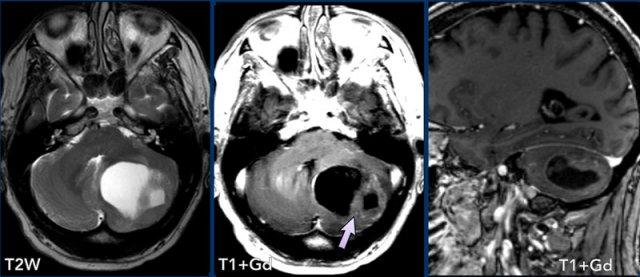

Các hình ảnh này của một phụ nữ 63 tuổi mắc bệnh von Hippel-Lindau.

Hãy quan sát kỹ. Dấu hiệu nào khó nhận thấy?

Hình ảnh

Có một nang lớn với một nốt nhỏ ngấm thuốc ở bán cầu tiểu não phải.

Thành nang không ngấm thuốc.

Lưu ý nốt u nằm ở phía màng mềm (mũi tên).

Có thêm hai nốt nhỏ ngấm thuốc ở mặt sau của tiểu não.

Đa u hầu như luôn liên quan đến bệnh von Hippel-Lindau.

Các hình ảnh này của một nam giới 29 tuổi.

Tổn thương dạng nang với thành không ngấm thuốc và một nốt ngấm thuốc nằm ở phía màng mềm.

Kết luận

Hình ảnh điển hình của u nguyên bào mạch máu.

Khi phẫu thuật cắt bỏ khối u này, phẫu thuật viên chỉ cần lấy bỏ phần nốt.